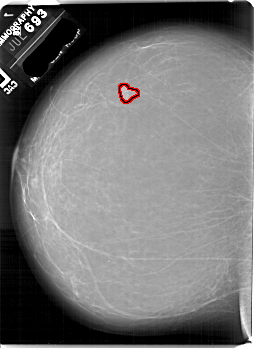

A_1882_1.RIGHT_MLO

RIGHT_CC LINES 6706 PIXELS_PER_LINE 4636 BITS_PER_PIXEL 12 RESOLUTION 43.5 NON_OVERLAY

FILE: A_1882_1.LEFT_CC.OVERLAY

TOTAL_ABNORMALITIES 1

ABNORMALITY 1

LESION_TYPE MASS SHAPE LOBULATED MARGINS CIRCUMSCRIBED

ASSESSMENT 3

SUBTLETY 5

PATHOLOGY BENIGN

TOTAL_OUTLINES 1

BOUNDARY